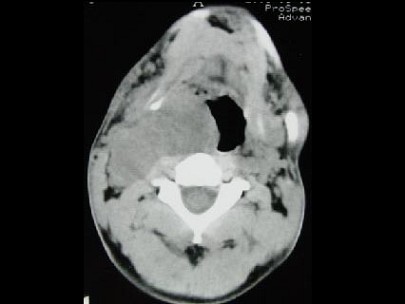

男,41岁,右侧咽部不适两年余,有异物感,声音嘶哑,CT如图所示,最可能诊断为 ( ) EBH-00941.jpg EBH-00942.jpg EBH-00943.jpg EBH-00944.jpg

题型: 单选题 分类: 耳鼻喉(头颈外科)学

• A.咽旁转移癌

• B.咽旁神经鞘膜瘤

• C.颈动脉体瘤

• D.咽旁淋巴瘤

• E.小唾液腺瘤